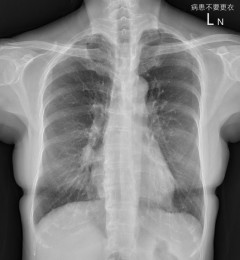

轻度咳嗽半年不当事 X光片竟查出3公分肺癌

胸腔科接收一名60岁不抽烟女性患者,轻微的咳嗽半年多没好,结果进行计算机断层,发现是3公分的肺癌,大概第二期或三期。...【浏览全文】